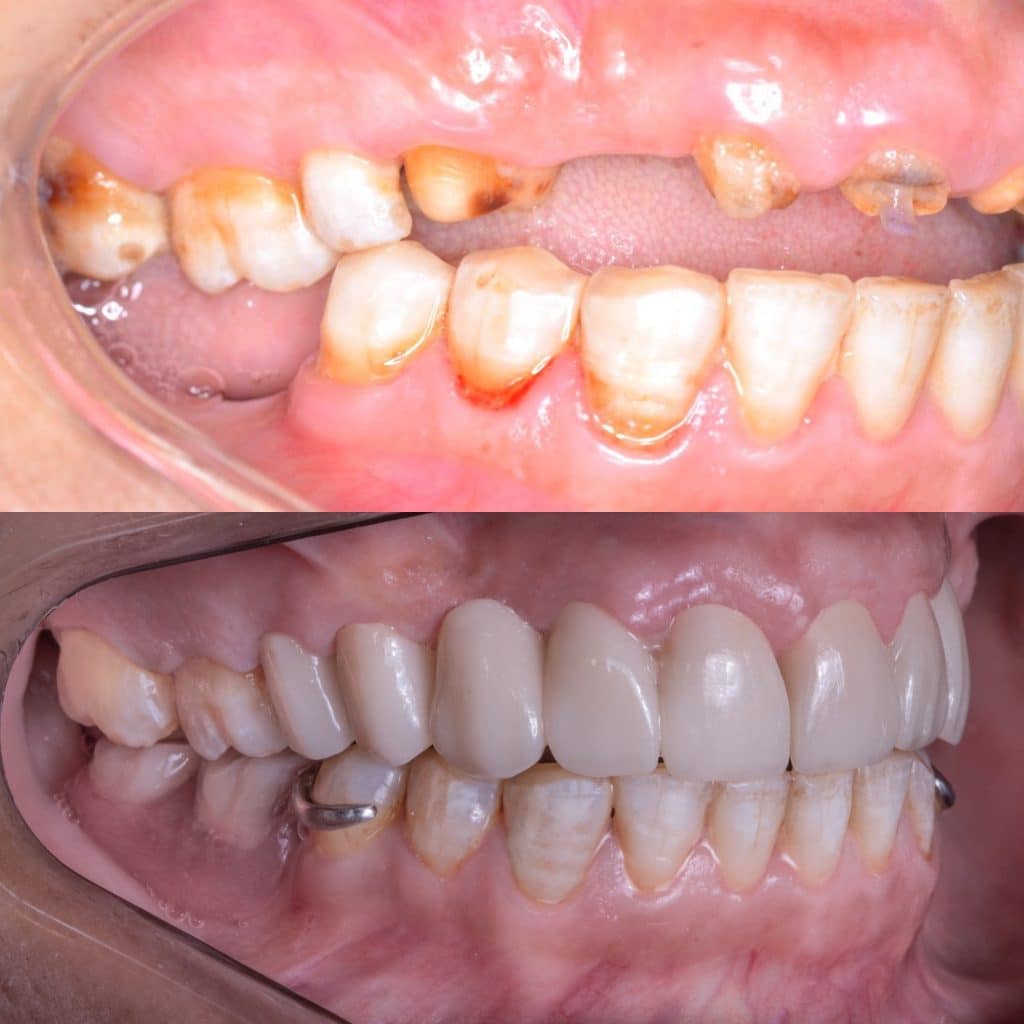

Full mouth rehabilitation case by 5th grade Dental student

42 years old female patient came to Pharos university in Alexandria egypt suffering from badly destructed teeth seeking her teeth to be restored

She lost her self confidencedue after losing her FPD for more than 2 years and she couldn’t smile or even eat !

The remaining tooth structure were broken with its old fiber posts due to malocclusion

- Peridontal treatment ( scaling and root planning )

- Extractions for non restorable teeth 11,20

- Surgical crown lengthening

- Transitional denture fabrication to restore the occlusion